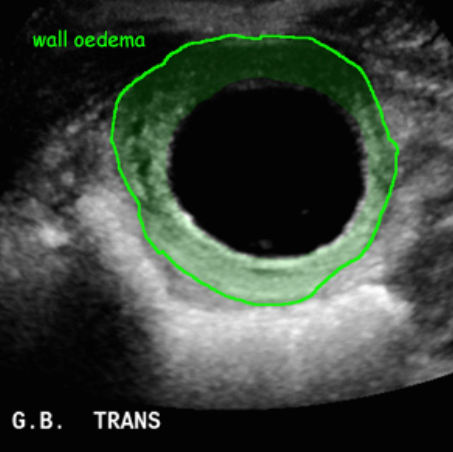

급성담낭염 US finding

- 담낭벽이 두꺼워진다 ( GB wall thickness 3mm 이상)

- GB내강의 압력증가 및 확장 (width 5cm 이상)

- color doppler 시 GB wall 혈류증가 GB lumen bile sludge (내부에코증가)